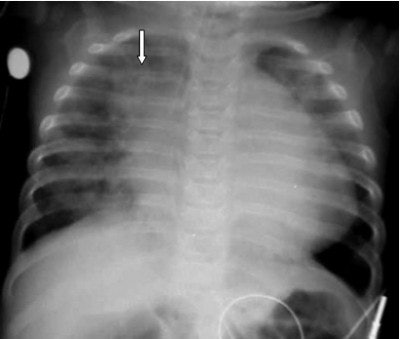

![]() |

| Figure 5 |

In figure 5 we have the chest x-ray of a six-month-old infant with cough, fever, and shortness of breath (SOB). Nine pairs of ribs are visible, the arms are raised above the child’s head, and there is no evidence of rotation. Pathologically, he has right upper lobe aspiration pneumonia (arrow). The darker area in the left lung base was diagnosed as a pneumothorax, cardiomegaly; something is displacing the ET tube to the right. A chest CT was recommended for further evaluation.